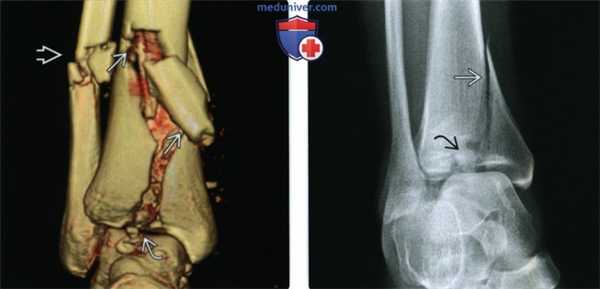

(Слева) Рентгенограмма голеностопного сустава в иммобилизирующей повязке, выполненная в проекции суставной щели. Определяется типичная картина: линия перелома проходит вертикально через центральный отдел нижней суставной поверхности большеберцовой кости и косо в дистальном отделе ее диафиза. Часто перелом дистального метаэпифиза большеберцовой кости сочетается с переломом малоберцовой кости.

(Справа) У этого же пациента при рентгенографии голеностопного сустава в боковой проекции визуализируются еще одна линия перелома, ориентированная в коронарной плоскости, и вдавление центрального отдела нижней суставной поверхности большеберцовой кости. (Слева) У этого же пациента при КТ в аксиальной плоскости определяется множество линий переломов. Томограмма позволяет оценить протяженность повреждения центрального отдела нижней суставной поверхности. Поскольку перелом был открытым, между костными фрагментами выявляются небольшие пузырьки воздуха.

(Справа) При КТ в сагиттальной плоскости визуализируется вдавление центрального отдела нижней суставной поверхности большеберцовой кости. Также выявляются фрагменты кортикального слоя, глубоко сместившиеся в костномозговую полость. Наличие данных фрагментов может воспрепятствовать выполнению репозиции.